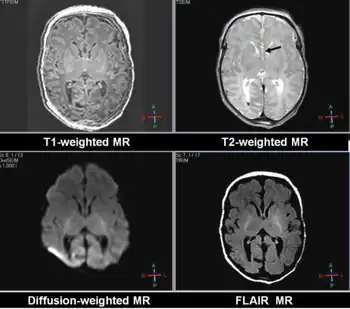

| a) Placental exam shows moderate villous hydrops and prenatal ultrasound showing polyhydramnios b) MRI shows Dandy-Walker malformation with cerebellar hypoplasia c)facial dysmorphism - high forehead, high arched eyebrows, strabismus, low-set ears, thin upper lip d) Sanger sequencing identified a homozygous novel GLDC variant c.707G > A p.(Arg236Gln) in the propositus | |